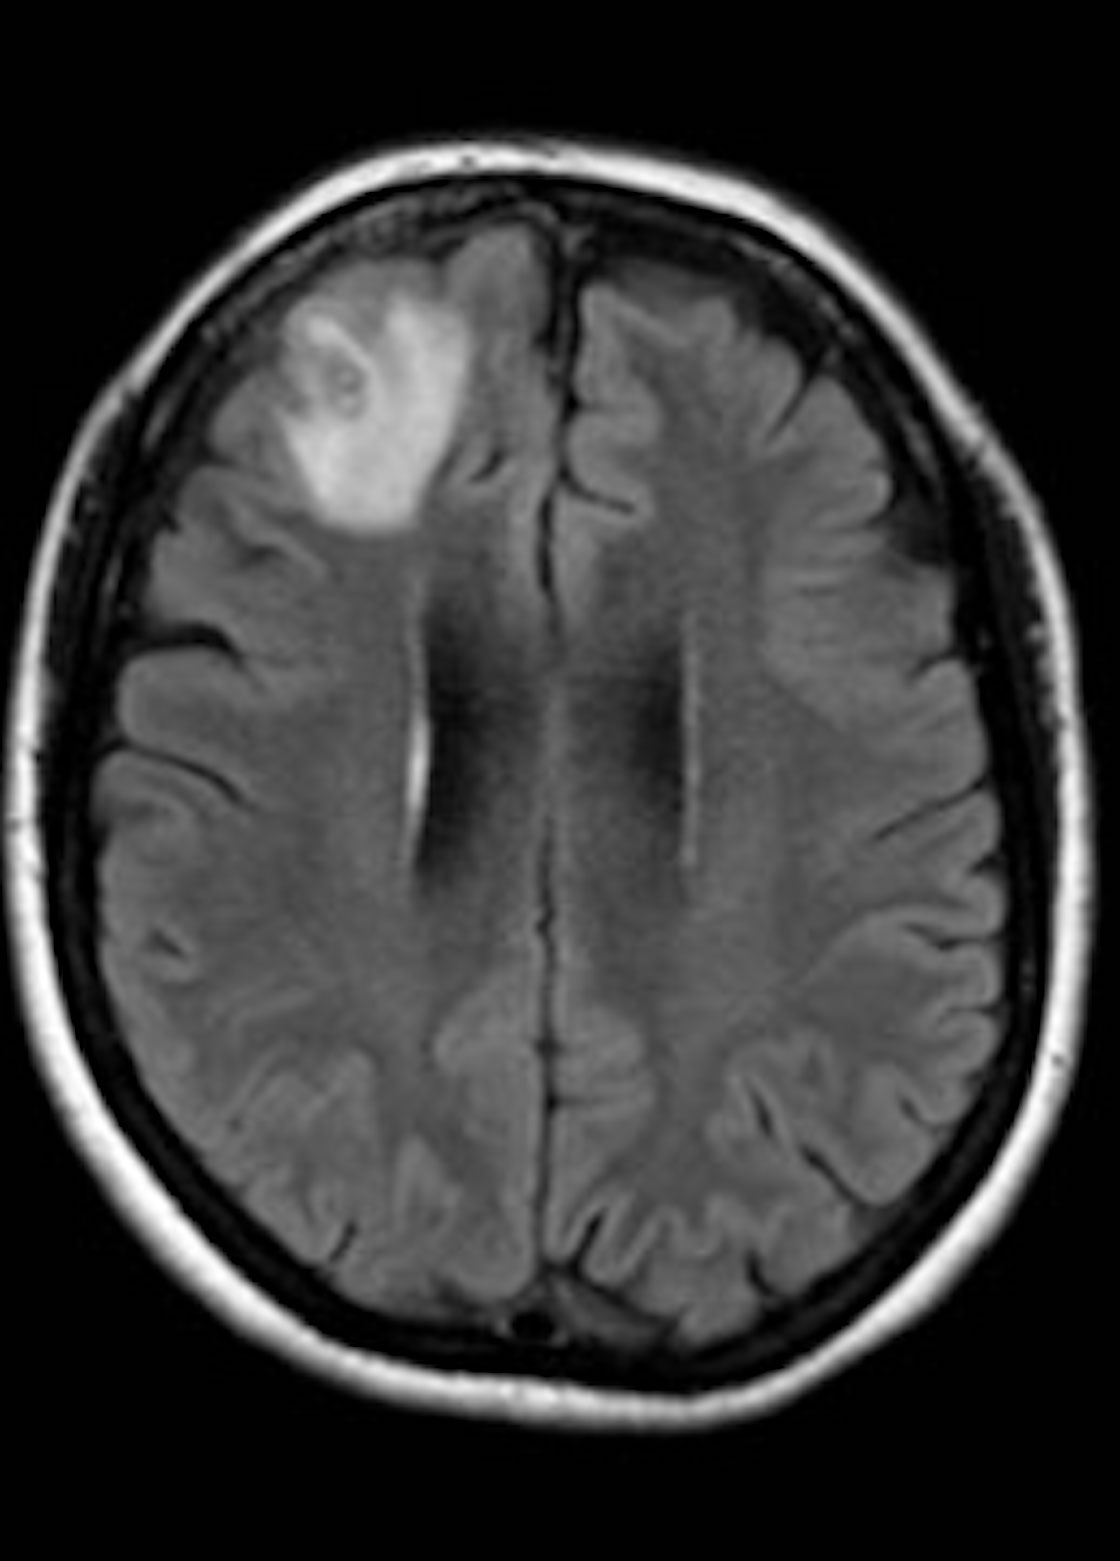

Y es que en un inicio, los doctores buscaban un posible tumor o incluso cáncer, o al menos eso dice el médico infectólogo Sanjaya Senanayake, coautor del estudio, a DW: “Esta paciente había sido tratada por una enfermedad misteriosa que, en última instancia, pensamos que era una afección inmunológica porque no habíamos sido capaces de encontrar un parásito y, de la nada, apareció este gran bulto en la parte frontal de su cerebro“.